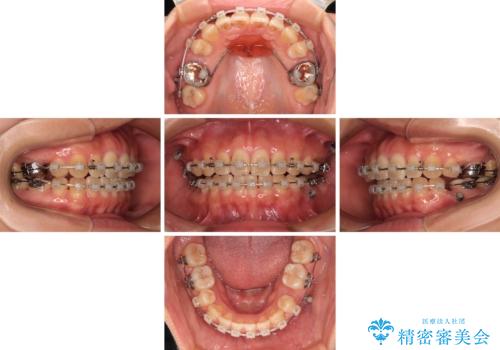

上顎左右の小臼歯2本および下顎小臼歯を1本抜歯し、補助装置を用いて上顎大臼歯が前方に移動しないように固定した上で、ワイヤー装置にて矯正治療を行うこととしました。

上下前歯のズレは舌の突出癖による影響も大きいと考えられたたため、舌のトレーニングをしっかりと行っていただきました。